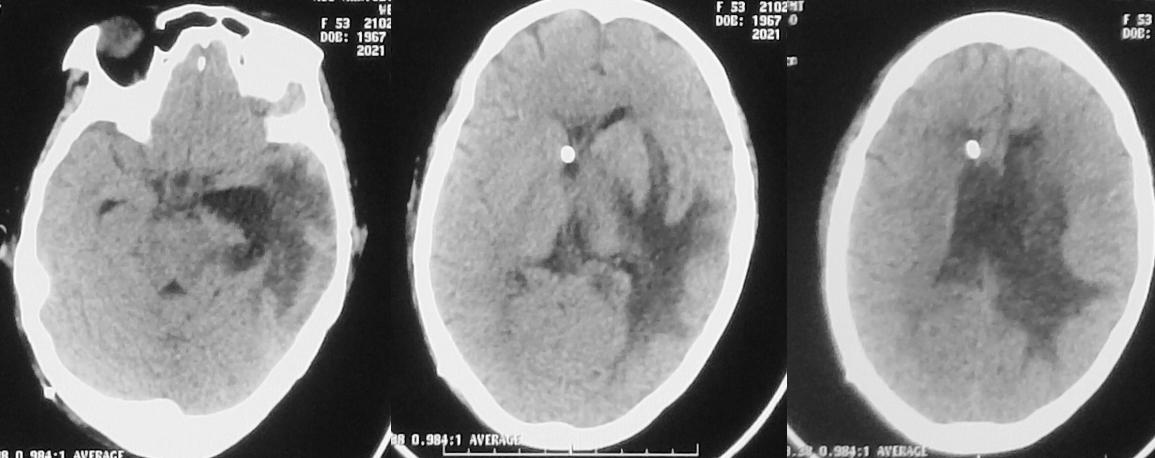

患者于2020年11月8日无明显诱因出现间断头痛。发病5天后,即2020年11月13日到当地的河南省潢川县某医院行头颅CT检查( 图-1 )发现左侧丘脑病变。

图-1: 2020年11月13日头CT

入院当天,患者出现恶心、呕吐数次,意识变差呈昏睡状态,强刺激才能睁眼。复查头颅CT见左侧丘脑病变增大,周围水肿明显,脑室扩张( 图-3 ),医生给予脑室穿刺外引流术。

图-3: 2020年11月21日头CT

脑室外引流术后第2天即2020年11月22日早上8点,患者好转为清醒,复查头颅CT见左侧脑室缩小( 图-4 );但患者出现发热,引流出的脑脊液浑浊,医生考虑患者丘脑病变为脑脓肿,给予头孢曲松抗炎治疗。

图-4: 2020年11月22日头CT

但当天晚上21:00,意识再次变差为嗜睡,复查头颅CT见脑室扩张( 图-5 ),考虑脑室引流不通畅,给予调整引流管后引流好转。

图-5: 2020年11月22日晚上头CT